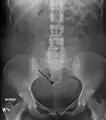

Two calcified fibroids (in the uterus) Two calcified fibroids (in the uterus)